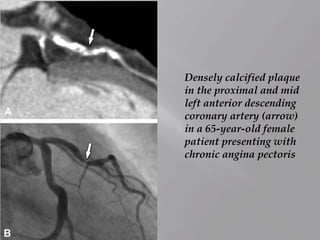

Densely calcified plaque

in the proximal and mid

left anterior descending

coronary artery (arrow)

in a 65-year-old female

patient presenting with

chronic angina pectoris